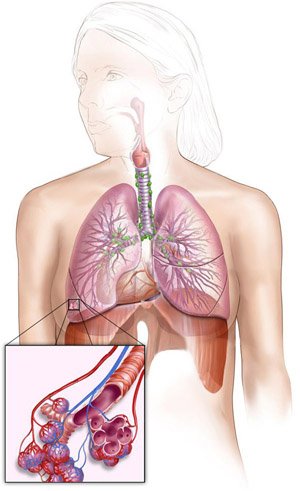

Фотографии заболеваний бронхолегочной системы